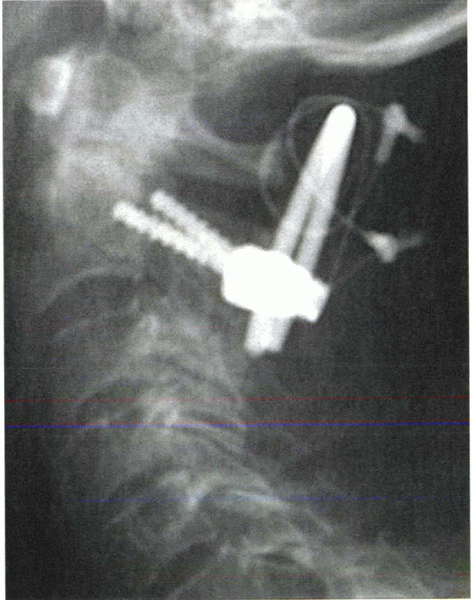

![]() |

|

Figure 28-10

In this example of C1-2 fusion, pedicle screws were placed into C2 through a posterior approach. Sublaminar wires secured C1 to a U-shaped rod connected to the pedicle screws and piece of bicortical iliac crest bone graft. |

pedicle screws into C1. These can be attached to C2 pedicle screws with

a rod. Polyaxial screws are ideal for this application. The starting

point for a C1 pedicle screw is approximately 2 cm from the midline,

aligned parallel to the sagittal plane. In contrast to C1-2

transarticular screws, the starting point for C2 pedicle screws is more

superior and along the lateral aspect of the C2 lateral mass (Fig. 28-10). The screw is angled medially to enter the C2 body. The vertebral artery

(lateral) and the spinal canal (medially) are at risk with screw misplacement.